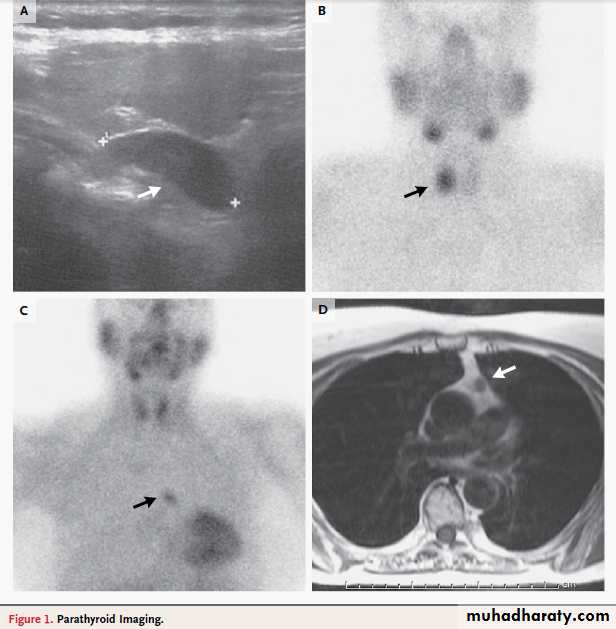

Panel A shows a longitudinal ultrasonographic image of the right thyroid lobe of the patient described in the vignette.

An enlarged parathyroid gland appears homogeneously solid and markedly more hypoechoic than the adjacent thyroid

tissue (arrow). Panel B shows a delayed-phase planar sestamibi scan indicating a marked uptake at the level of the right thyroid lobe, where the ultrasound localized the parathyroid lesion (arrow) in the patient described in the vignette. Panels C and D show a mediastinal parathyroid adenoma in a 65-year-old woman with primary hyperparathyroidism.

In Panel C, a delayed-phase sestamibi scan shows a marked uptake at the level of the middle mediastinum

(arrow). In Panel D, a magnetic resonance imaging scan (T1-weighted image) of the chest shows a lesion in the aortopulmonary window (arrow). The patient underwent a sternotomy, and a parathyroid adenoma was excised.

Neck imaging is not indicated for diagnosis,

but it is useful for disease localization beforeplanned parathyroidectomy (Fig. 1). Sestamibi

scanning and ultrasonography are used most

commonly.

The main advantage of sestamibi scanning is that it may localize ectopic parathyroid.